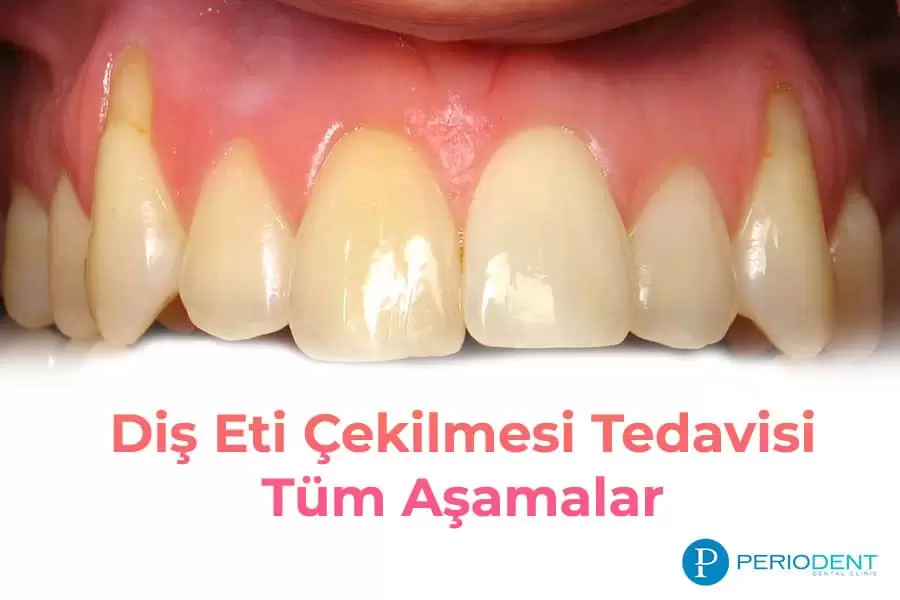

Diş Eti Çekilmesi Nedir? Nasıl Tedavi Edilir?

[caption id="attachment_6893" align="alignleft" width="350"] diş eti çekilmesi[/caption]Diş Eti Çekilmesi Nedir?Diş eti çekilmesi, dişleri saran ...

Diş Eti Çekilmesi Tedavisi Nasıl Yapılır?

Diş eti çekilmesi sık karşılaşılan diş sağlığı sorunlarından biridir. Diş eti çekilmesi tedavisi, diş eti çekilme nedeni teşhis edildikten sonra planl...